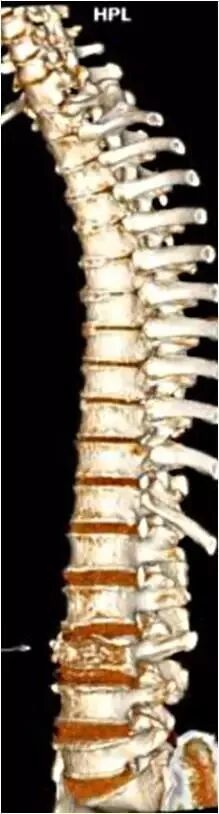

高清全方位骨科检查

西门子双源CT(SOMATOM Drive)可以用于全方位骨科检查。最新ADMIRE基于原始数据域的迭代重建技术,不仅可以大幅降低图像噪声,还可以降低辐射剂量。